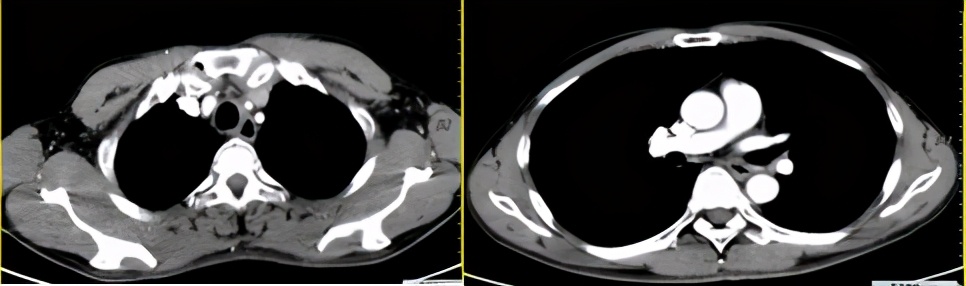

疗效评价:大PR

放化疗后第一次随访影像对比(左:治疗前;右:治疗后)

免疫维持治疗CT检查(2021.3)